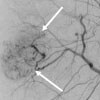

Vascular Malformation

- Conditions: Arteriovenous malformation (AVM), Hereditary Hemorrhagic Telangiectasia (HHT)

- Services: Angiography, embolization